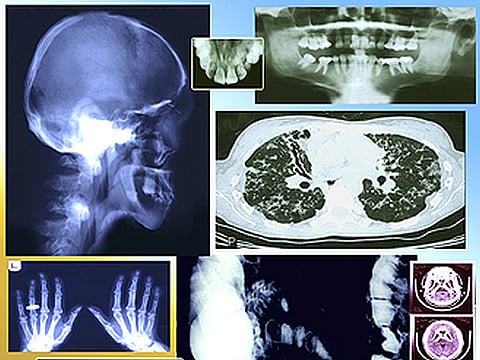

MIÉRCOLES, 23 de enero de 2019 (HealthDay News) -- Un sistema de inteligencia artificial (IA) puede analizar las radiografías de tórax y detectar a los pacientes que deben recibir una atención inmediata, informan unos investigadores.

El sistema también podría algún día reducir los retrasos en los hospitales. Las radiografías de tórax conforman un 40 por ciento de todas las imágenes diagnósticas en el mundo, y puede haber grandes retrasos, según los investigadores.

Montana y sus colaboradores utilizaron más de 470,300 radiografías de tórax de adultos para desarrollar un sistema de IA que pudiera identificar los resultados inusuales.

El rendimiento del sistema en la priorización de las radiografías se evaluó en una simulación que usó un set distinto de 15,887 radiografías de tórax. Para proteger la privacidad del paciente, se eliminó toda la información de identificación de las radiografías.

El sistema tuvo una alta precisión al distinguir las radiografías de tórax anómalas de las normales, señalaron los investigadores. Las simulaciones mostraron que con el sistema de IA, los hallazgos críticos recibieron una opinión de un radiólogo experto en un promedio de 2.7 días, frente a un promedio de 11.2 días en la práctica real.